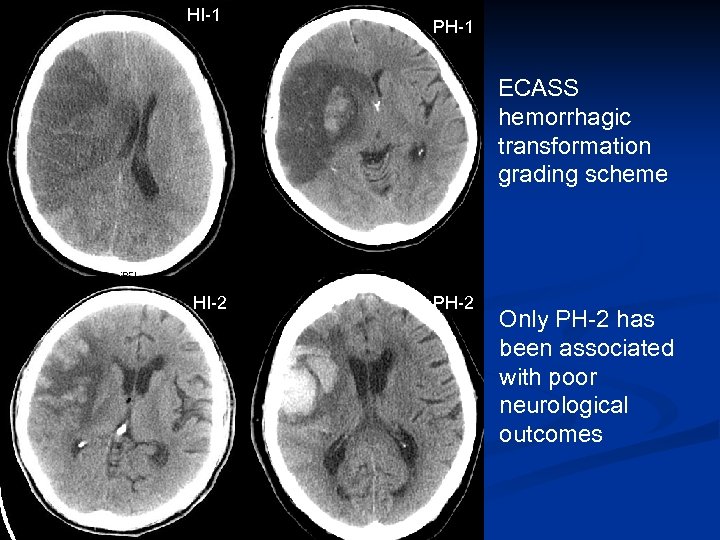

HI-1 PH-1 ECASS hemorrhagic transformation grading scheme HI-2 PH-2 Only PH-2 has been associated with poor neurological outcomes

Neurologic Complications of Stroke n Hemorrhagic conversion (~36 hours). (Fiorelli M, Stroke 2001) n n RF of HC: large infarct, cardio-embolic, elevated glucose, thrombolytic (Stroke 2008; 39: 2249) Mass effect and cerebral edema. Occurs in up to 10% and peaks at day 2 -5 (Vahedi K, Lancet Neurol 2007). n RF: high NIHSS, > 50% MCA infarction, early N/V (Stroke 2001) Recurrent stroke (rare) n Seizures: more common with hemorrhagic stroke n INFECTION/Toxic metabolic n